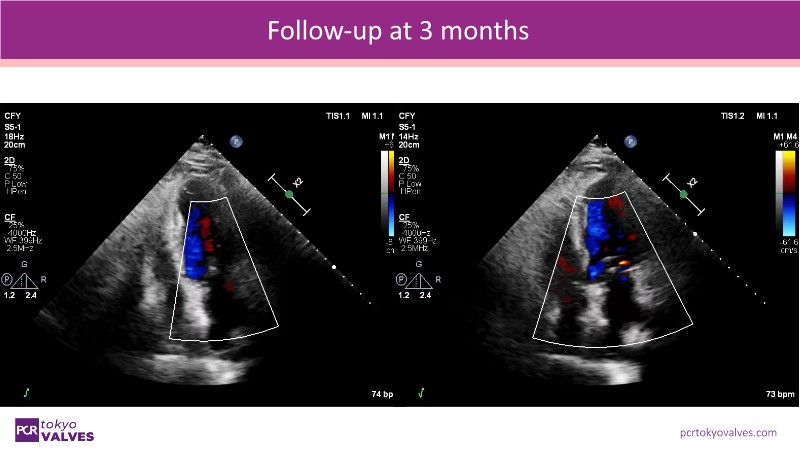

Explore the latest advancements in TEER therapy with this PCR Tokyo Valves 2025 session dedicated to MitraClip. Through expert-led case discussions, gain a deeper understanding of complex scenarios, including restricted posterior leaflet in functional mitral regurgitation, commissure lesion (A3P3), and MitraClip combined with Amulet.

This session also highlights key findings from the OCEAN study, shedding light on 1-year heart failure rehospitalisation outcomes with MitraClip. Additionally, discover how atrioventricular valve morphology impacts treatment strategies and how the four available clip sizes can be used to personalise and optimise TEER outcomes.